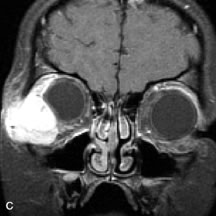

Lymphomas have MRI characteristics similar to those of inflammatory lesions in that they are hypointense to fat and isointense to muscle on T1-weighted images (Fig. 22). They may appear hyperintense to fat on T2-weighted images, perhaps owing to less fibrosis than that seen in orbital inflammatory pseudotumor, although this is not a consistent finding.31,50,66 Lymphoid tumors typically enhance moderately after contrast injection. Unfortunately, studies have shown that tumor density and homogeneity are similar between inflammatory and malignant orbital infiltrates, and MRI cannot differentiate these lesions.72,73

Fig. 22. A and B. T1- and (C) T2-weighted MR scans demonstrate a poorly defined multicompartmental mass enveloping the lateral rectus, superior rectus, and levator palpebrac superioris muscles. The lesion is isointense to brain on T1- and T2-weighted scans, as is typical for highly cellular neoplasms. D. Postcontrast fat-suppressed T1-weighted scan demonstrates intense enhancement of the infiltrating intraconal and extraconal tumor.